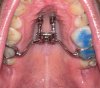

Bin gerade vom KFO zurück - der Distraktor ist jetzt drin. Sitzt auf zwei Schrauben und 17+27. Ist ein Modell, das auf die Zähle draufgeklebt wird und nicht mit Bändern, was ich sehr angenehm finde. Ich kann es absolut nicht leiden, wenn etwas zwischen die Zähne geschoben wird :D

Also OP am 21.08. Am 28.08. soll ich dann wieder zum KFO und wir werden mit dem drehen beginnen. Es sollen 5-6mm werden, also ca. 1 Woche. Daher ist der nächste Termin dann am 04.09., wo es kontrolliert und ggf. fixiert wird. Am 16.10. soll ich die Brackets im OK bekommen. So ist aktuell die Planung.

Sind die Metallwände nicht doch zwischen 6 und 7 bzw 7 und 8 eingeklemmt?

Eingeklemmt nicht. Liegen nur sehr eng an, sind aber nur mit dem Kleber befestigt.